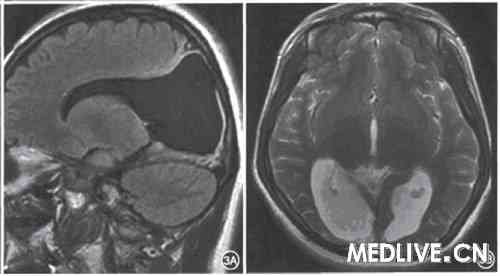

患者女,23岁,自幼发现视力不佳,智力发育迟滞。于2009年5月22日前来就诊。否认产伤及头部外伤史。眼科检查:双眼矫正视力0.05,双侧视乳头萎缩。瞳孔等大等圆,直径约3 mm,对光反射灵敏。神经系统检查:神志清楚、言语流利,简易智能量表MMSE评分20。mtDNA3个原发位点突变11778、14484、3460均为阴性。转诊神经科行头颅MRI发现双侧枕叶皮质明显萎缩,侧脑室后角扩大,双侧视神经信号萎缩变细(图3)。

图3皮质盲患者头颅MRI检查,3A示矢状位Flair加权, 3B示轴位T2加权,均显示双侧枕叶皮质萎缩,侧脑室后角扩大

图3皮质盲患者头颅MRI检查,3A示矢状位Flair加权,

3B示轴位T2加权,均显示双侧枕叶皮质萎缩,侧脑室后角扩大